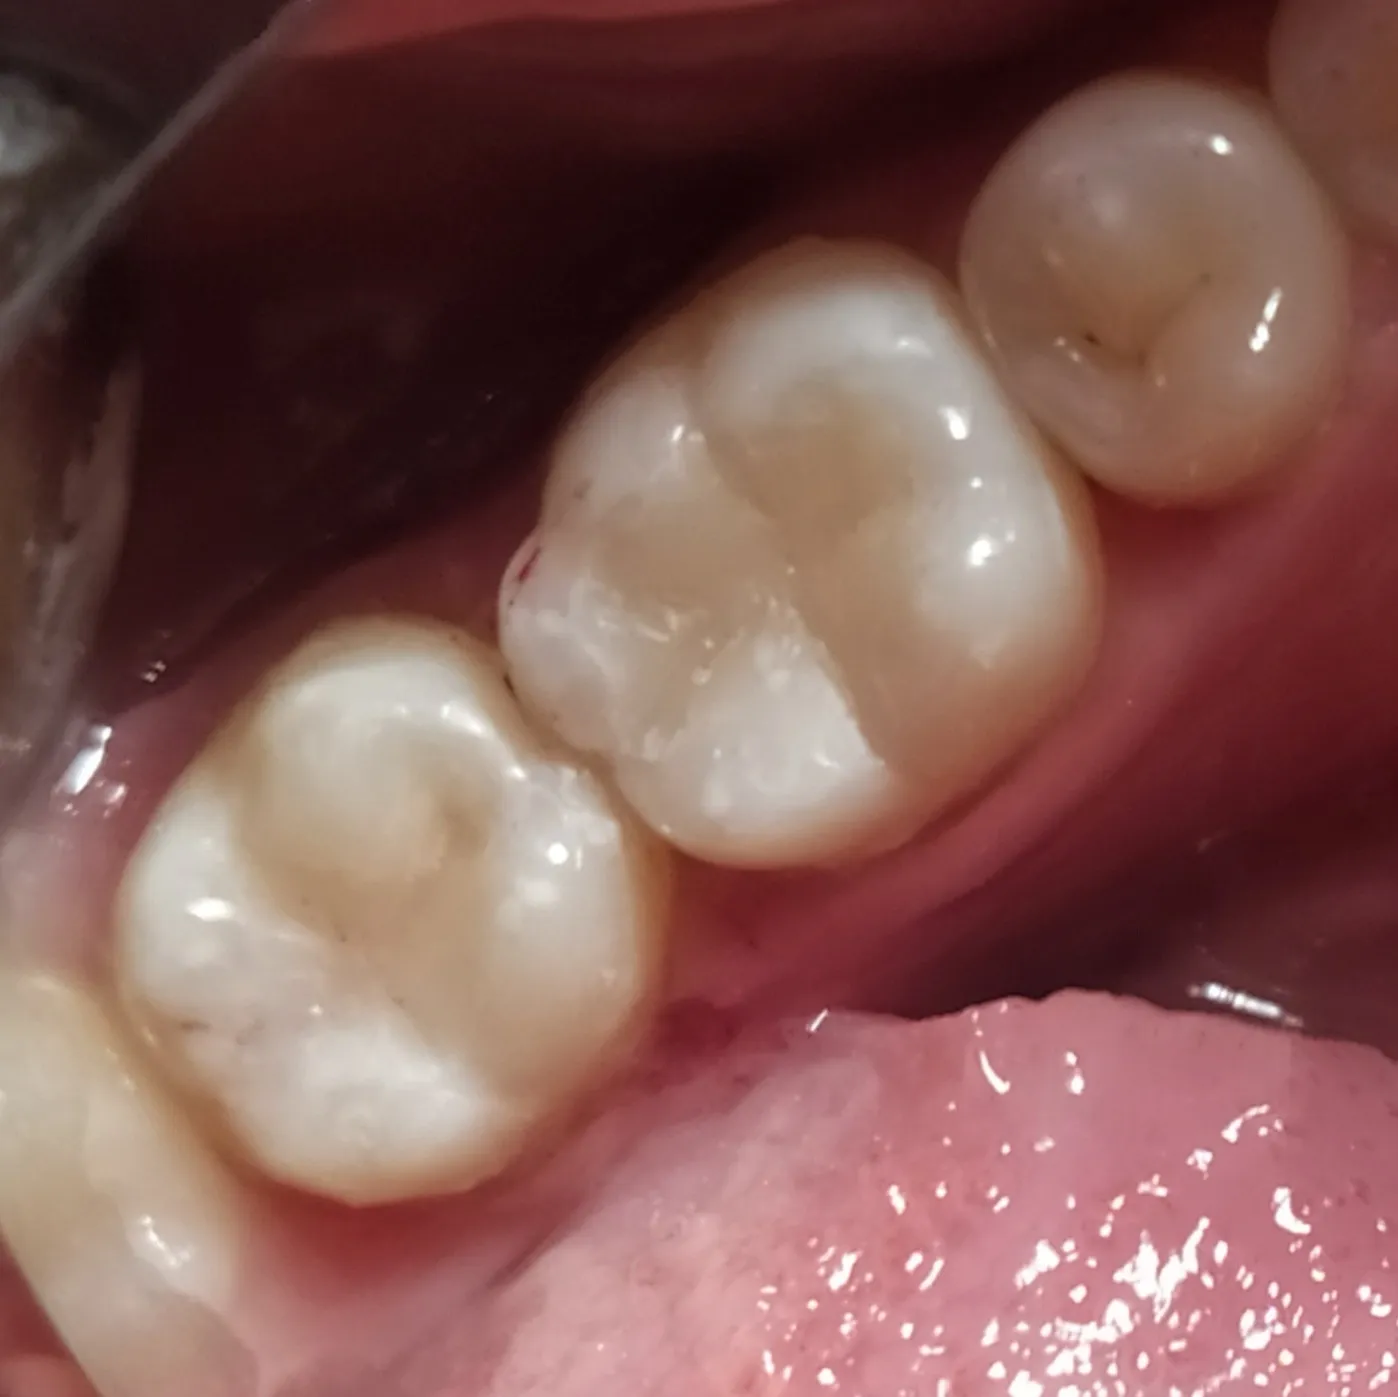

В ходе лечения были проведены следующие работы:

- эндодонтическое лечение с применением коффердама

- постоянная пломбировка трех корневых каналов

- временное восстановление коронковой части зуба 3.7

- даны рекомендации по установке коронки